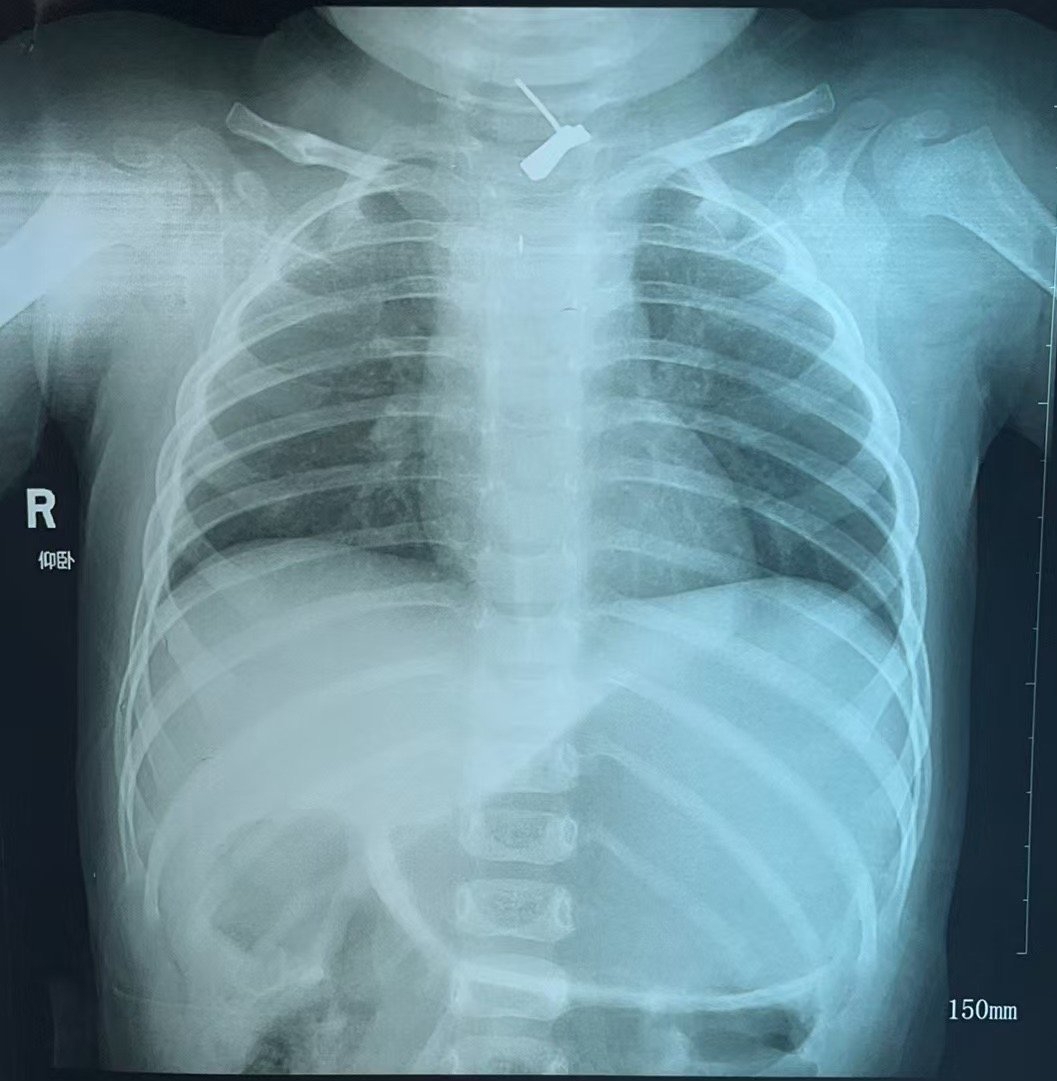

12月16日,1岁半女童贝贝(化名)被家长送往四川大学华西医院急诊,后收入小儿外科。经检查,胸部X片提示贝贝“食管异物嵌顿”,胸部CT提示贝贝食管上段异物,周围管壁肿胀并积气,纵隔及颈部软组织肿胀积气,医生考虑贝贝食管有异物伴穿孔可能,可能存在感染。

华西医院揪出食管内“肇事”金属耳钉。华西医院供图